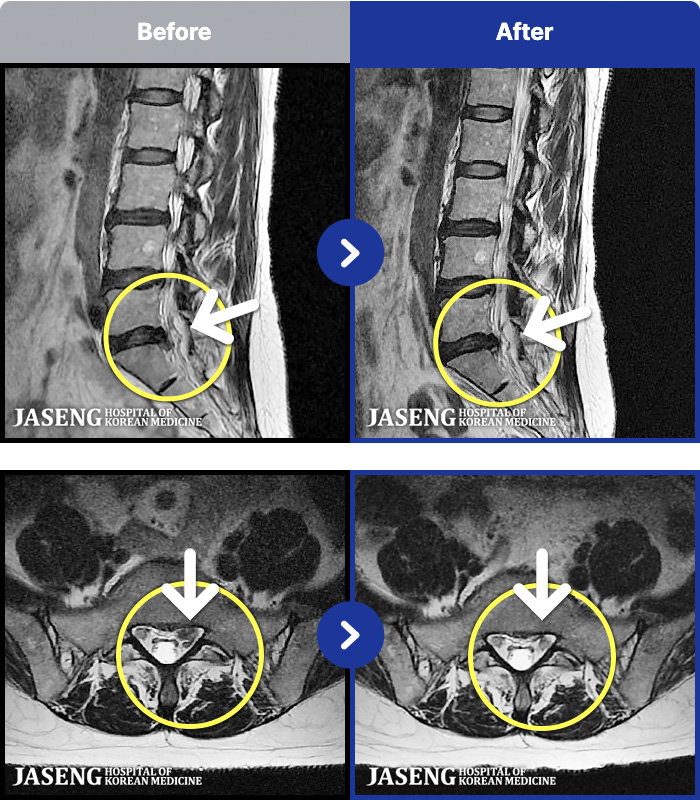

54 MRI ũ ʸ Ȯϼ.